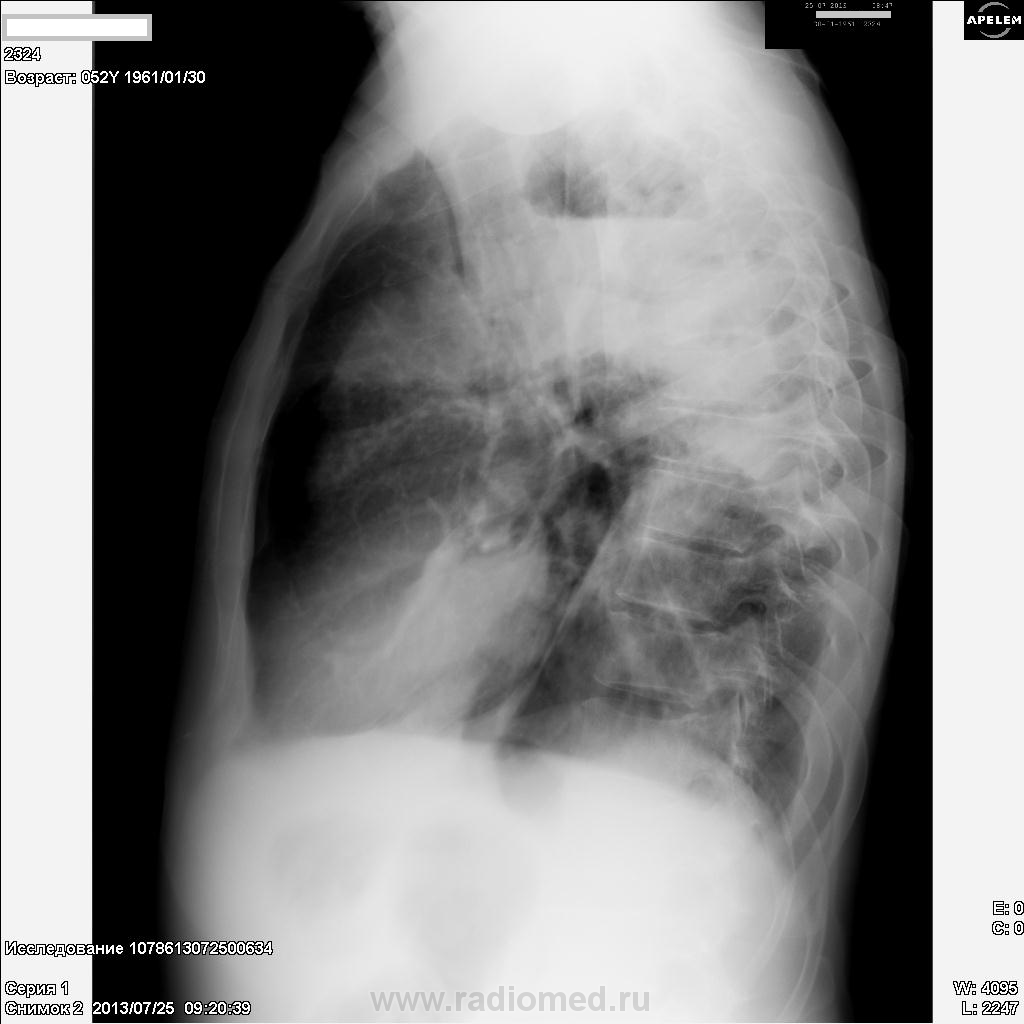

Пациент, 52 года. Поступил в т/о с диагнозом: Пневмония. Анализов еще нет. Со слов, болен три дня: кашель, слабость, небольшая лихорадка, одышка. Снимки от сегодня.

Предварительно картину можно расценить, как  полисегментрную абссцедирующую пневмонию, не исключается параканкрозный характер процесса.Показана бронхоскопия.

Деструктивная пневмония,держать в уме рак.Справа игра теней или пневмоторакс.

Я бы еще ателектаз верхней доли слева добавил...

На мой взгляд картина абсцесса

Как вариант: рентгенпризнаки абсцесса верхней доли левого легкого на фоне нарушения бронхиальной проходимости.

Левосторонняя тотальная пневмония, осложненная абсцедированием в S1-2 в фазе дренирования (горизонтальный уровень в полости распада), с преобладанием инфильтративных изменений в S1-2 и S4-5, с ограниченным гидротораксом в главной междолевой щели и гиповентиляцией легкого. Пациен, видимо, кахексичен. Неплохо бы возбудителя высеять, да и динамика интересна. Чем лечат?

Безусловно,абсцесс верхней доли слева.Есть онконастороженность,ниже абсцесса вероятны округлые тени.Туберкулёза нет.Поздравляю Вас,Дмитрий, с полученными ЛТГ.Нам,наверное,надо их не мельчить.Будем делиться дальнейшим опытом.